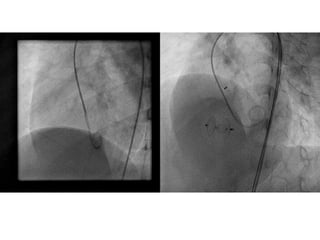

Courtsey: Trong Phi Li, MD

AMPLATZER® Membranous VSDOccluder 2 Device Sizes 18 available sizes:  9 waist diameters: 4-10,12,14mm  2 rims: 1mm & 3mm  All sizes have a 3 mm waist length Rim Waist Diameter Waist Length

• 94.

Nit-Occlud Le VSDcoil  Coil design with attached polyester fibres  Outstanding adaptation properties  Broad range of different sizes (8 – 16 mm distal diameter)  Small delivery system (6 to 7 Fr)  No CHB reported – High flexibility

• 105.

Device Selection  Distaldiameter (D) at least twice the minimal diameter of the VSD on the right ventricular side and 1–2 mm greater than, the diameter of the VSD at the LV side.  P = proximal, D = distal

• 106.

Limitations  PMVSD <8 mm at the RV end  Aneurysm formation is mandatory  Absence of PHT